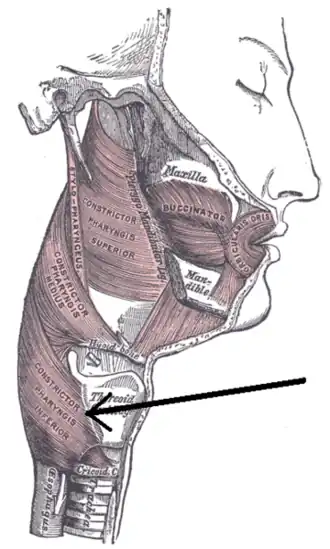

Muscles of the pharynx (throat)and cheek. (Constrictor pharyngis inferior visible at bottom left.) | |

Killian's dehiscence (also known as Killian's triangle) is a triangular area in the wall of the pharynx between the cricopharyngeus (upper esophageal sphincter (UES)) and thyropharyngeus (Inferior pharyngeal constrictor muscle) which are the two parts of the inferior constrictors (also see Pharyngeal pouch). It can be seen as a locus minoris resistentiae. A similar triangular area between circular fibres of the cricopharyngeus and longitudinal fibres of the esophagus is Lamier's triangle or Lamier-hackermann's area.